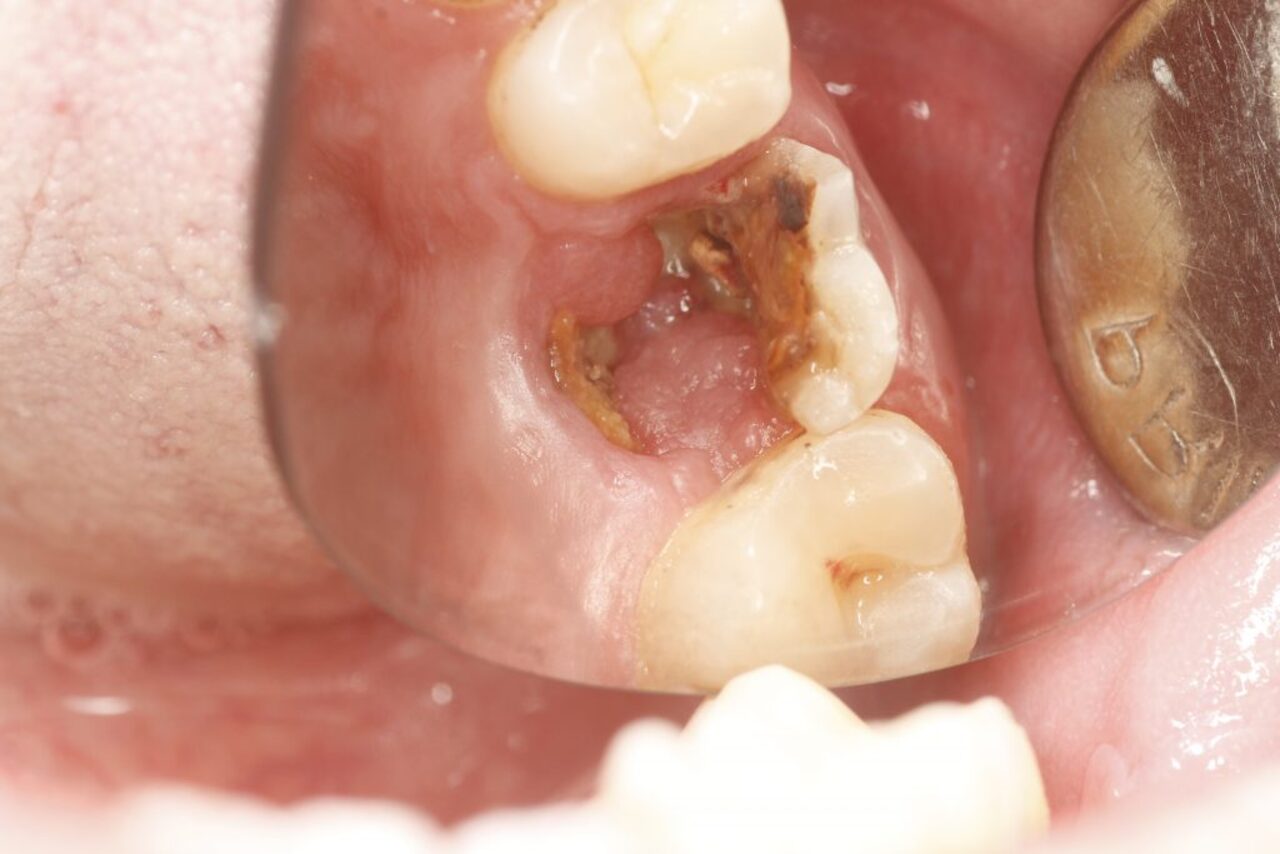

Trường hợp răng hàm bị sâu và chân răng hoàn toàn bị phá hủy

Nếu chân răng sau khi khám cho thấy đã bị hoàn toàn phá hủy thì có thể sẽ phải nhổ bỏ răng hàm bị sâu. Trước khi thực hiện, các bác sĩ cần phải tính toán kỹ lưỡng về rủi ro có thể gặp phải, đặc biệt nếu răng cần nhổ lại chính là chiếc răng cấm.

Răng hàm bị sâu đã hoàn toàn bị phá hủy